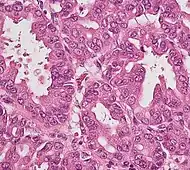

Histopathology

The most common form of pancreatic cancer (adenocarcinoma) is typically characterized by moderately to poorly differentiated glandular structures on microscopic examination. There is typically considerable desmoplasia or formation of a dense fibrous stroma or structural tissue consisting of a range of cell types (including myofibroblasts, macrophages, lymphocytes and mast cells) and deposited material (such as type I collagen and hyaluronic acid). This creates a tumor microenvironment that is short of blood vessels (hypovascular) and so of oxygen (tumor hypoxia).[2] It is thought that this prevents many chemotherapy drugs from reaching the tumor, as one factor making the cancer especially hard to treat.[2][3]

Cancer type | Relative incidence[11] | Microscopy findings[11] | Micrograph | Immunohistochemistry markers[11] | Genetic alterations[11] |

---|---|---|---|---|---|

Pancreatic ductal adenocarcinoma (PDAC) | 90% | Glands and desmoplasia | ![]() | ||

Pancreatic acinar cell carcinoma (ACC) | 1% to 2% | Granular appearance | ![]() |

||

Adenosquamous carcinoma | 1% to 4%[58] | Combination of gland-like cells and squamous epithelial cells. | ![]() | Positive for:

Negative for: |

|

Pancreatic neuroendocrine tumor | 5% | Multiple nests of tumor cells | ![]() | ||